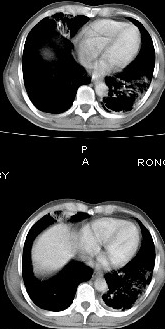

男68岁,反复发热、咳嗽,咯痰1月,曾有咯血史,双肺闻及呼吸音增粗。

左肺上叶尖后段及下叶多发实变阴影,内见支气管充气征,段以上支气管尚通畅,肺门区未见软组织肿块影,结合病人有反复发热病史,首先考虑感染性病变(干酪性肺炎不能排除),建议抗炎治疗后复查或结合纤支镜检查。

左肺上叶尖段及下叶干酪性肺炎可能性大,建议结合临床相关检查.右肺中叶炎症.建议治疗后复查.

该患者在25天前外圆平片见右肺中上肺野大片状影,(治疗不祥,在反复问病史后患者告诉;近一月住在新房内,搞装修),我认为首先考虑是感染,而且过敏性肺炎可能性大。